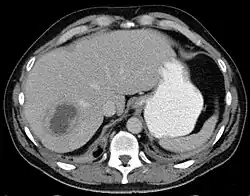

Liver abscess on axial CT image: a hypodense lesion in the liver with peripherally enhancement. | |